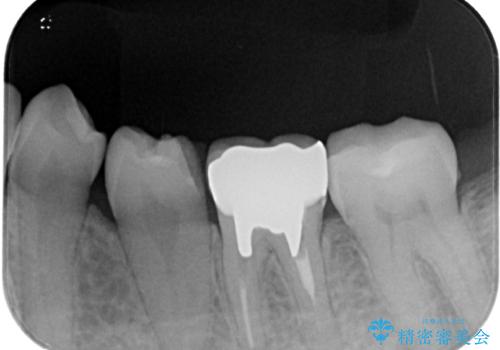

土台の材料を外して顕微鏡下で確認したところ、歯根にまで及ぶ破折が認められたため、インプラント治療を行うこととしました。

他にも銀歯や欠損となっている歯に対しての治療も希望されたため、補綴治療を行うこととしました。